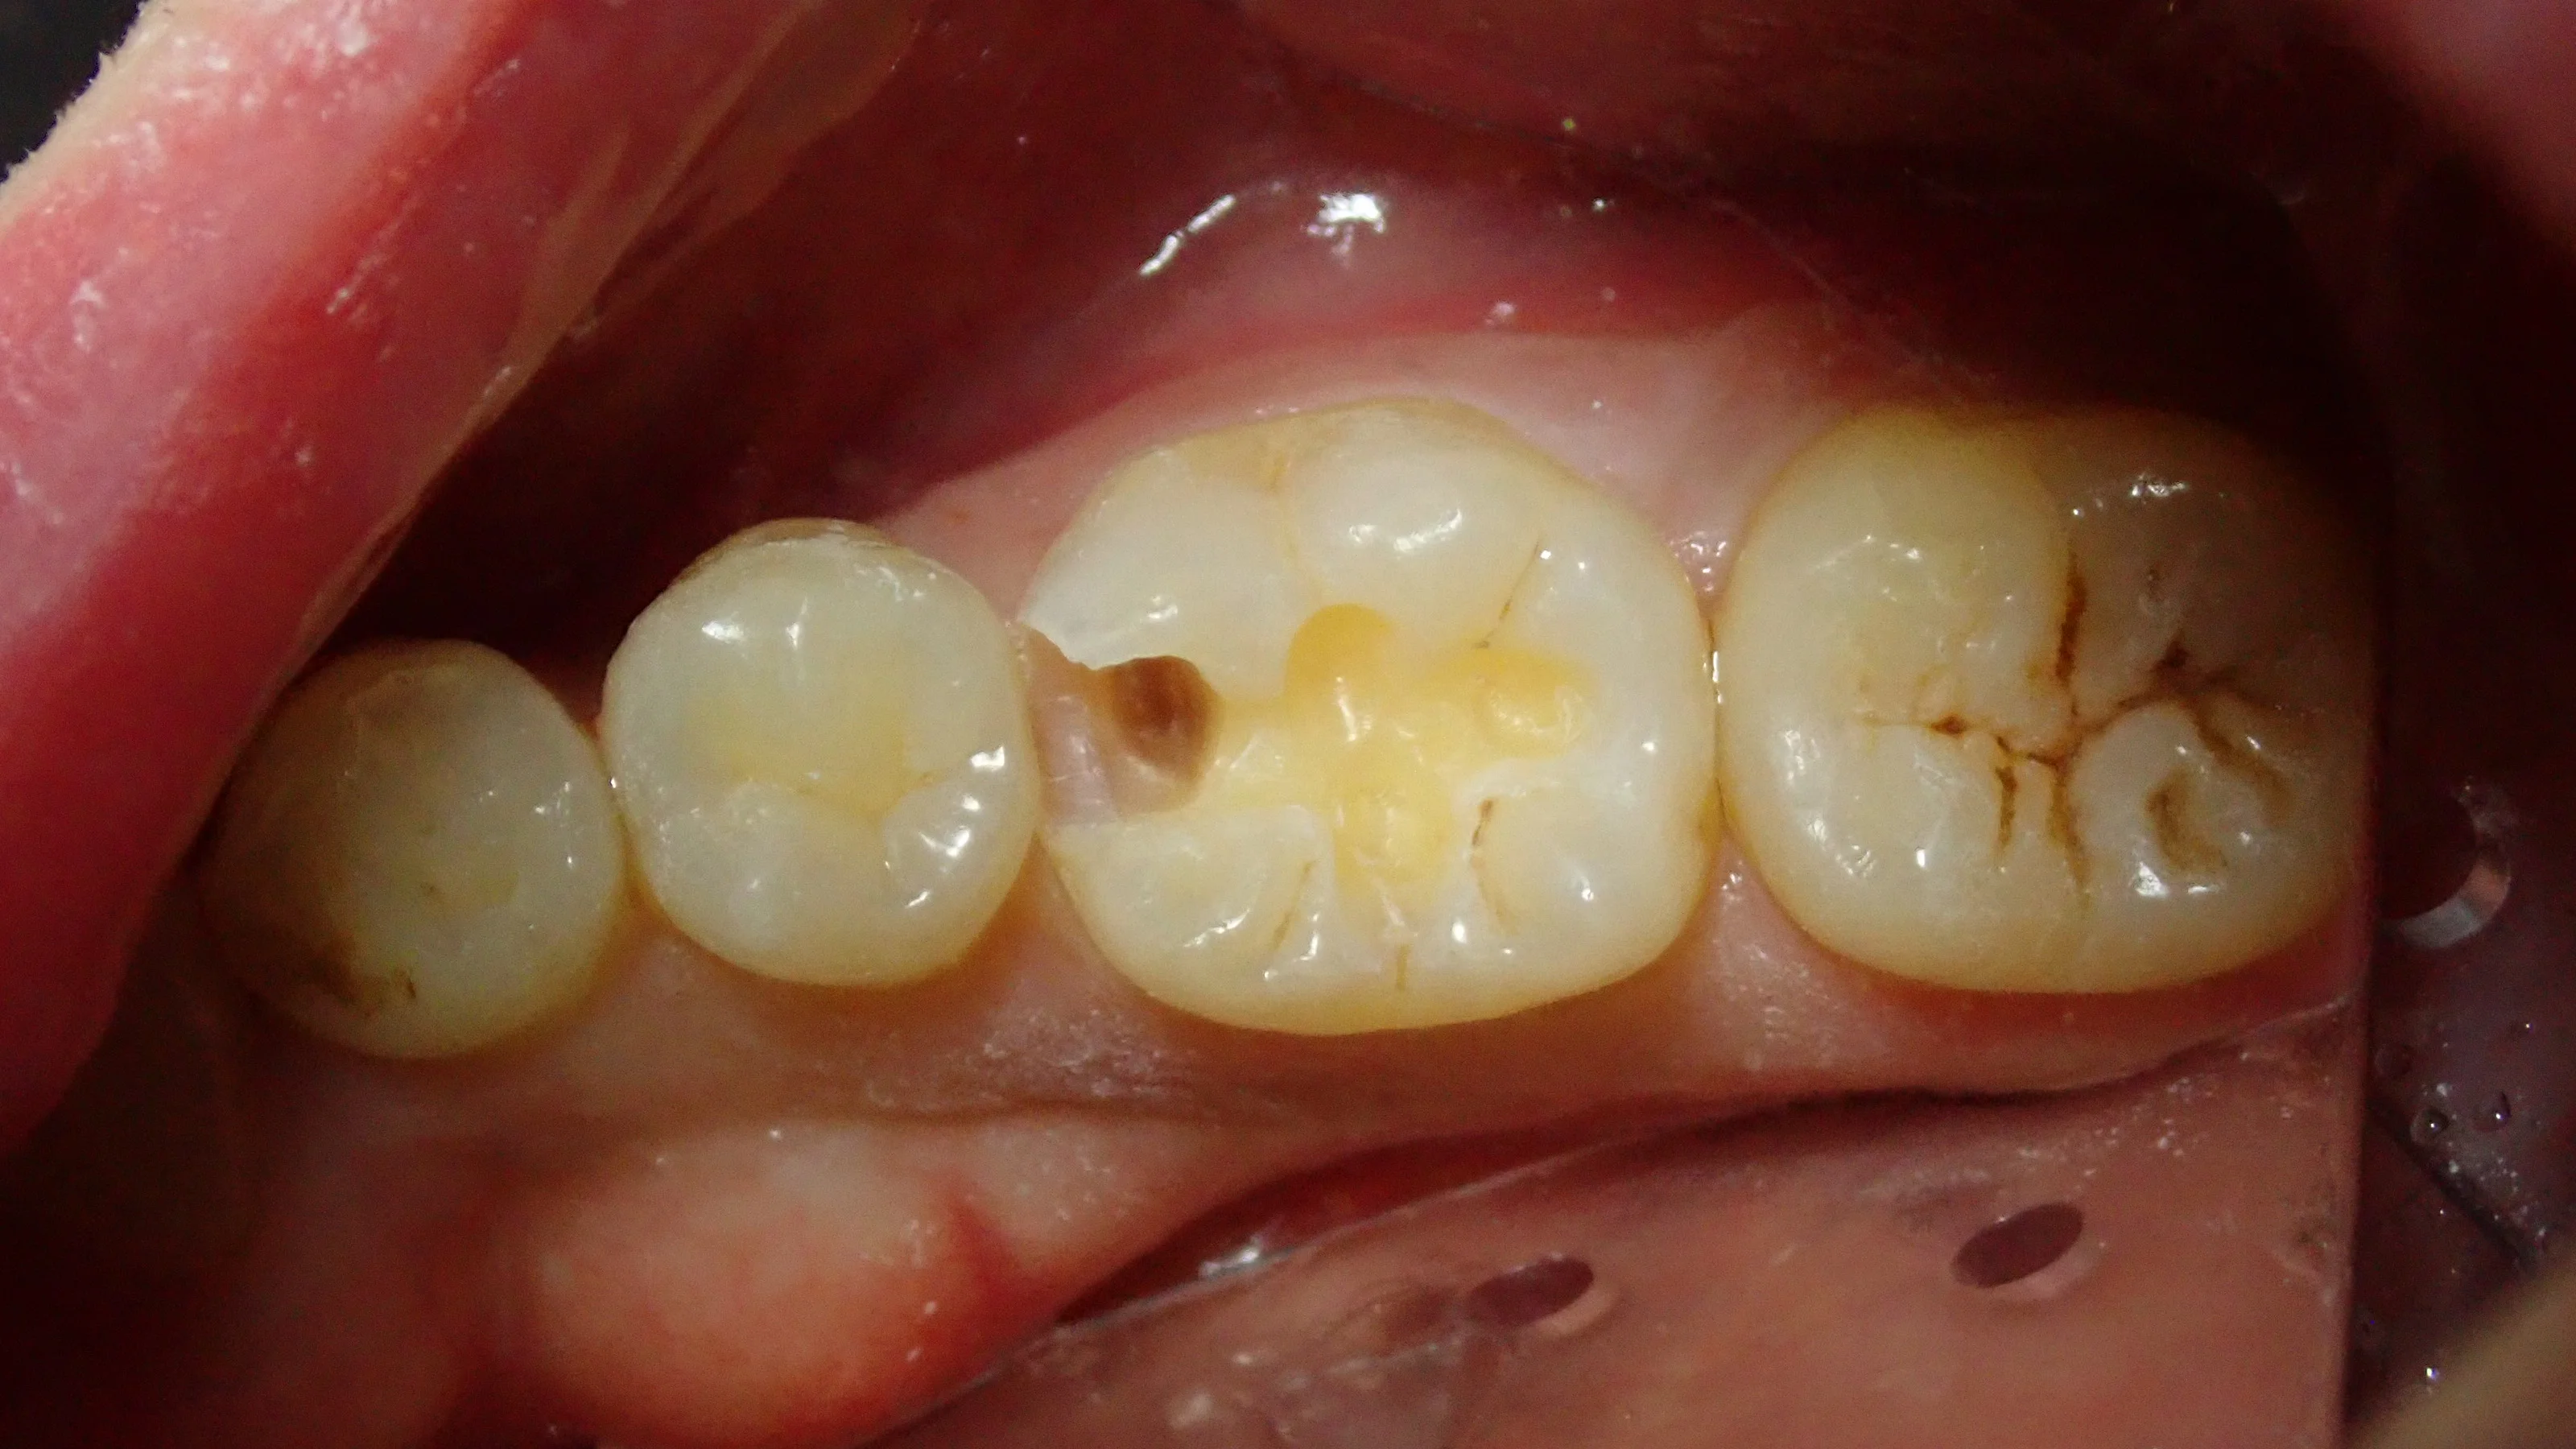

充填後に咬合調整を終えた写真です。

比較的良い感じにステイニング(溝の部分の着色等)も出来たと思います。

そして最後に、術前術後の比較写真がこちらです。

仕上がりにご満足いただけたようで、次回4月に右上の奥歯を行う事となりました。

歯の間の部分もフロスを通しても引っ掛かりが全くない様に仕上げましたので、しっかりとフロスを通していただいて大丈夫です!